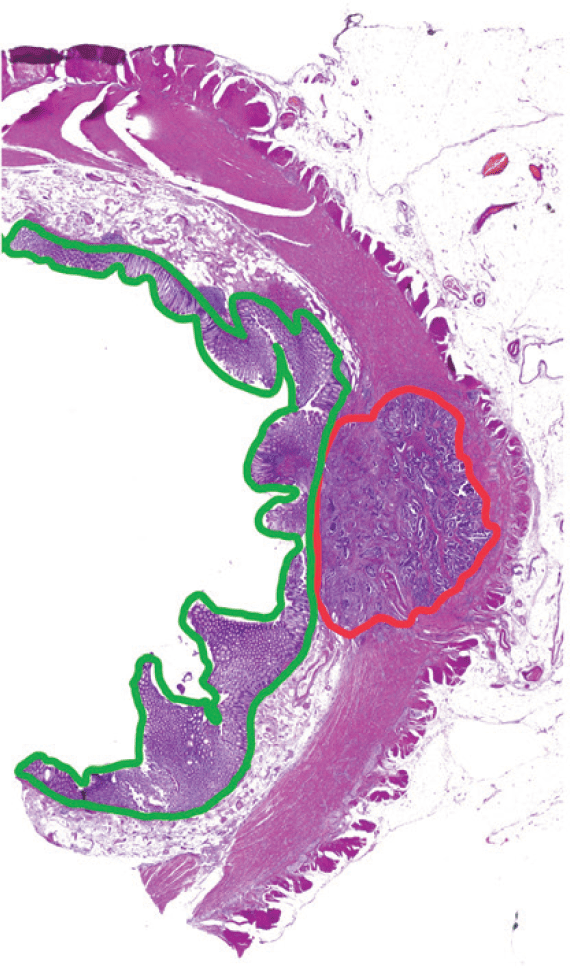

Representative images of H&E stained colorectal tumour showing spatial enrichment using Laser Microdissection (LMD).

(1) Prior to dissection

(2) Areas of interest annotated

(3) Tissues dissected

Figure 1: (1) Patient sample prior to dissection under the LMD. (2) Patient sample with tumour regions (red) and adjacent normal tissues (green) annotated to be microdissected. (3) Patient sample after all tissues of interest were dissected and collected into a 0.6 mL tube cap, with muscular/ adipose tissues remaining in the section. Magnification 2.5x.

Laser microdissected samples were captured with cut areas of approximately 100 × 106 μm2 for ~ 20μg of protein from colorectal cancer and normal adjacent samples (Figure 1). Digested samples were purified using StageTips, then reconstituted in 0.1% FA.